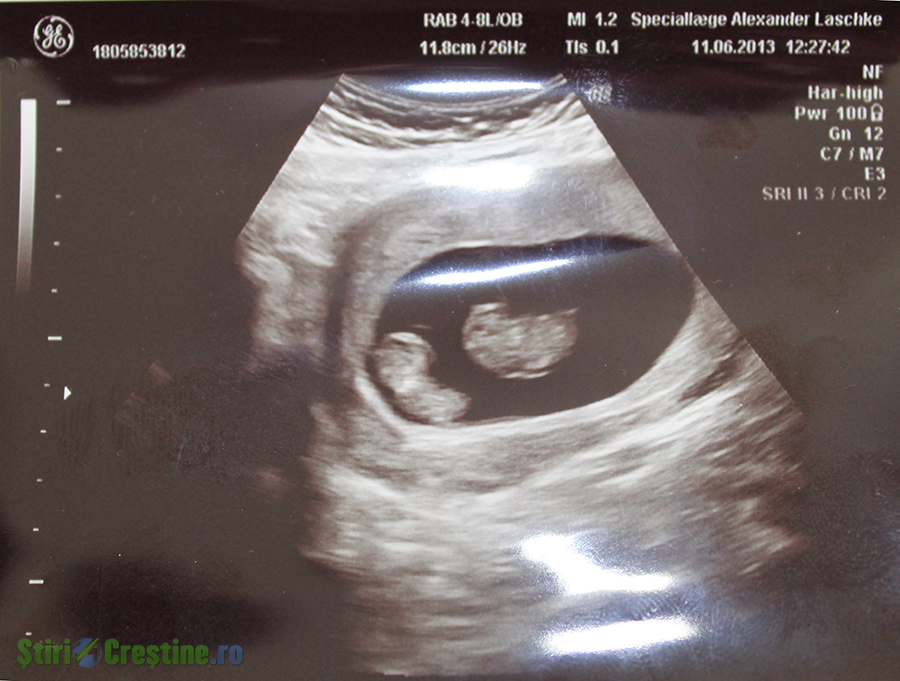

Lacrimile îmi curg pe obraz și acum, când scriu aceste cuvinte. Eram cea mai fericită. Ne doream al doilea copil și eram însărcinată. La prima ecografie ni s-a confirmat, dar la o a doua ecografie eram în al nouălea cer pentru că eram însărcinată cu gemeni (doi băieți). Nu pot exprima în cuvinte ceea ce am simțit.

Pe 11 iulie 2013 am mers împreună cu soțul să ne vedem bebelușii, aveam gemeni identici. În acel moment asistenta ce mi-a făcut scanarea ne-a spus că bebelușii sunt bolnavi de un sindrom foarte rar de care ei au studiat doar în cărți și nu au avut niciun astfel de caz în spital (noi locuind în Danemarca). Ni s-a spus că este ceva foarte grav și să așteptăm să vină un medic specialist să ne spună mai multe. Două ore de așteptare au fost un calvar. Timpul stătea în loc. În sfârșit medicul a venit și ce ne-a spus că nu era de bine. Era din ce în ce mai rău. Bebelușii aveau sindromul transfuziei de sânge. Un bebeluș primea prea mult sânge și celălalt prea puțin. Nu era bine nici pentru unul, nici pentru celălalt. Sindromul sever era mult prea devreme instalat și nu se putea face niciun tratament. “Trebuie să vă așteptați ca la următoare ecografie unul din copii sau ambii să nu mai fie în viață”, acestea au fost cuvintele medicului.